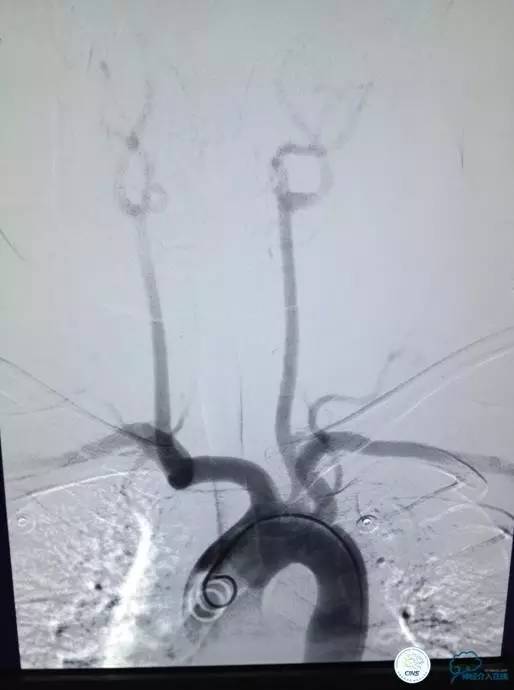

▼L-CCA

▼R-VA